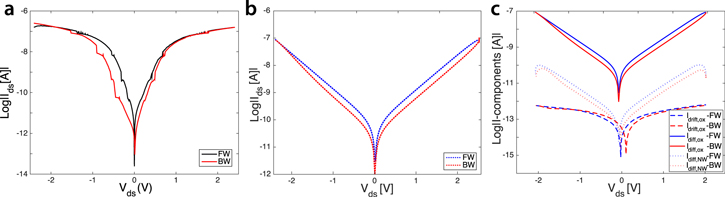

Characterization of the biofunctionalization process was performed both by observation with SEM and fluorescence imaging. In figure 2 we report the SEM micrographs of one of the fabricated devices (a) before and (b) after surface biomodification. From figure 2(b) it is clearly evident the formation of a biolayer of AB around the nanostructure. Figure 3(a) shows the semi-logarithmic Ids–Vds curve of one fabricated SiNW device. The Ids–Vds curve presents a hysteresis loop that is pinched at  V for devices with bare surfaces (black curve), and is clear mark of a memristive system [10, 11]. Once functionalized with ABs, the I–V curve of the sensor changes (figure 3(a)); a non-zero current is now observed when the voltage is swept back to zero (red curve), which is different from the initial condition of zero current at zero voltage. The pinched loop is lost and replaced by a voltage gap defined by the difference in voltage between the crossing points of the forward and backward Vds curves with the x-axis. When the sensor is exposed to a solution of specific AG, then washed, dried and measured, a shrinking of the voltage gap is clearly visible. This shrinking is dependent on the concentration of the target molecule, as demonstrated by the calibration curve reported in figures 3(b) and (c). Details on the sensing protocol and the electrical acquisition are reported in section I of the SI. It is important to observe that all the measurements are performed in air, under fixed relative humidity conditions [9] that are kept constant by continuous monitoring in a sealed measurement chamber. This set-up avoids contamination and creates stable conditions for repeatability of the experiment. Note that a number of control experiments are performed with the aim of defining the electrical noise introduced by interfering species. For example, the effect of silanization on the voltage gap variation has been acquired and, by comparison, estimated to be negligible with respect to the voltage gap modification measured after AB functionalization and AG uptake. Testing the effect of the blocking step with gelatin would lead to further information on the charge-based behavior of the AB–AG complex. In figure 3(b) the experiment consisted of in-air sensing, with the voltage gap technique, of the cancer marker vascular endothelial growth factor (VEGF), diluted in PBS solution in very low concentrations (fM). Figure 3(c) reports the most recent results achieved in the detection of small amount (75–150 fM) of rabbit AG dispersed in the more challenging environment of a breast TE. The TE is prepared directly from patient biopsies (see the SI for details on the TE preparation process), with formation of a cell lysate that is then used for sensing once diluted in PBS, without any kind of filtering. The final concentration of the detected AG in the TE is extremely challenging considering the 100 000 fold mass excess of nonspecific tumor proteins. Data illustrated in figure 3(c) demonstrate the capability of this novel technique in profiling very small concentration changes after interaction with a real biological sample. To the best of our knowledge, the literature reports very few works on immuno-biosensors based on SiNWs capable of measuring femtomoles of AGs in a complex sample such as a TE. Most of the high-sensitive results have been achieved with SiNW-FETs for the detection of RNA with DNA based probes [28]. Very recently, SiNW-FET based in-air immuno-biosensors have been demonstrated as a valid candidate for the highly sensitive detection of cancer markers in real patient samples [23]. However, these results are based on the electrical measurement of the conductance according to the state-of-the-art ISFET technology. In this article we intend to report, for the very first time, an interesting alternative to the femtomolar detection in real breast TEs with memristive immuno-based SiNWs. Memristive nanowires have already been proposed for memory and computation applications but never as ultra-highly sensitive biosensors for detection in breast tumor tissues.

V for devices with bare surfaces (black curve), and is clear mark of a memristive system [10, 11]. Once functionalized with ABs, the I–V curve of the sensor changes (figure 3(a)); a non-zero current is now observed when the voltage is swept back to zero (red curve), which is different from the initial condition of zero current at zero voltage. The pinched loop is lost and replaced by a voltage gap defined by the difference in voltage between the crossing points of the forward and backward Vds curves with the x-axis. When the sensor is exposed to a solution of specific AG, then washed, dried and measured, a shrinking of the voltage gap is clearly visible. This shrinking is dependent on the concentration of the target molecule, as demonstrated by the calibration curve reported in figures 3(b) and (c). Details on the sensing protocol and the electrical acquisition are reported in section I of the SI. It is important to observe that all the measurements are performed in air, under fixed relative humidity conditions [9] that are kept constant by continuous monitoring in a sealed measurement chamber. This set-up avoids contamination and creates stable conditions for repeatability of the experiment. Note that a number of control experiments are performed with the aim of defining the electrical noise introduced by interfering species. For example, the effect of silanization on the voltage gap variation has been acquired and, by comparison, estimated to be negligible with respect to the voltage gap modification measured after AB functionalization and AG uptake. Testing the effect of the blocking step with gelatin would lead to further information on the charge-based behavior of the AB–AG complex. In figure 3(b) the experiment consisted of in-air sensing, with the voltage gap technique, of the cancer marker vascular endothelial growth factor (VEGF), diluted in PBS solution in very low concentrations (fM). Figure 3(c) reports the most recent results achieved in the detection of small amount (75–150 fM) of rabbit AG dispersed in the more challenging environment of a breast TE. The TE is prepared directly from patient biopsies (see the SI for details on the TE preparation process), with formation of a cell lysate that is then used for sensing once diluted in PBS, without any kind of filtering. The final concentration of the detected AG in the TE is extremely challenging considering the 100 000 fold mass excess of nonspecific tumor proteins. Data illustrated in figure 3(c) demonstrate the capability of this novel technique in profiling very small concentration changes after interaction with a real biological sample. To the best of our knowledge, the literature reports very few works on immuno-biosensors based on SiNWs capable of measuring femtomoles of AGs in a complex sample such as a TE. Most of the high-sensitive results have been achieved with SiNW-FETs for the detection of RNA with DNA based probes [28]. Very recently, SiNW-FET based in-air immuno-biosensors have been demonstrated as a valid candidate for the highly sensitive detection of cancer markers in real patient samples [23]. However, these results are based on the electrical measurement of the conductance according to the state-of-the-art ISFET technology. In this article we intend to report, for the very first time, an interesting alternative to the femtomolar detection in real breast TEs with memristive immuno-based SiNWs. Memristive nanowires have already been proposed for memory and computation applications but never as ultra-highly sensitive biosensors for detection in breast tumor tissues.

Standard image High-resolution imageFigure 3. The voltage gap detection approach. (a) The fully pinched hysteresis loop of a just fabricated SiNW (black curve) is lost when its surface is modified with AB (red curve). The adsorption of charged proteins is demonstrated by the augmented current peak and the appearance of a voltage gap. The voltage gap is a parameter of sensing; it decreases as a function of femtomolar concentrations of vascular factors in PBS (b), and as a result of the sensing of AG in the more challenging environment of a breast TE (c). The reported error bars stand for the standard deviation of multiple measures of the same sensor (b), and the standard deviation of the voltage gap acquisitions are related to three similar devices under the same exposure conditions (c).

First, we considered the case of bare nanodevices, and we compared a real Ids–Vds measurement acquired from a SiNW after the fabrication and before any modification with biological material (figure 6(a)) with a simulated characteristic (figure 6(b)). As clearly evident from the plots, the simulated curve fits well the experimental one and models pinched hysteretic behavior (figure 6(b)). Figure 6(c) illustrates the corresponding components of the total current calculated in the simulation, components that are strictly dependent on each other and that affect the total current with their continuous competition/compensation. In the diagram, both forward and backward branches of the current are shown in order to better demonstrate the similarities between the experimental and modeled curves under external voltage sweep.

Figure 6. Experimental (a) and simulated (b) Ids–Vds characteristics of a SiNW before any surface biomodification. Both curves have pinched hysteresis loops, similar to the hysteresis of memristive-like behavior, and same current peak. Blue and red curves denote the forward and backward current branches, respectively. (c) Corresponding components of the total current reported in (b). The parameters chosen for this simulation are:  Hz,